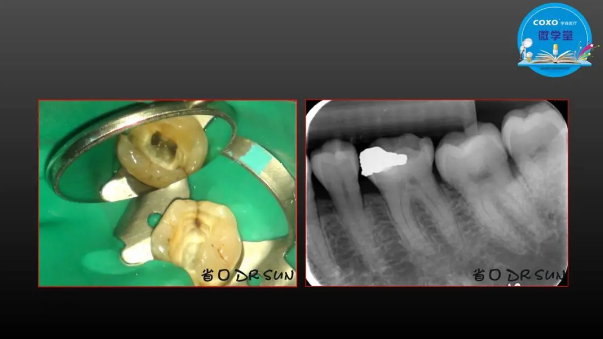

主講:孫書昱

主任醫(yī)師,牙體牙髓副主任, 廣東省口腔醫(yī)院牙體牙髓科 主任醫(yī)師。2003年碩士研究生畢業(yè),研究方向為牙體牙髓病學,擅長于牙體牙髓病的診斷、齲齒、牙髓炎、根尖周病的治療以及前牙美容修復。